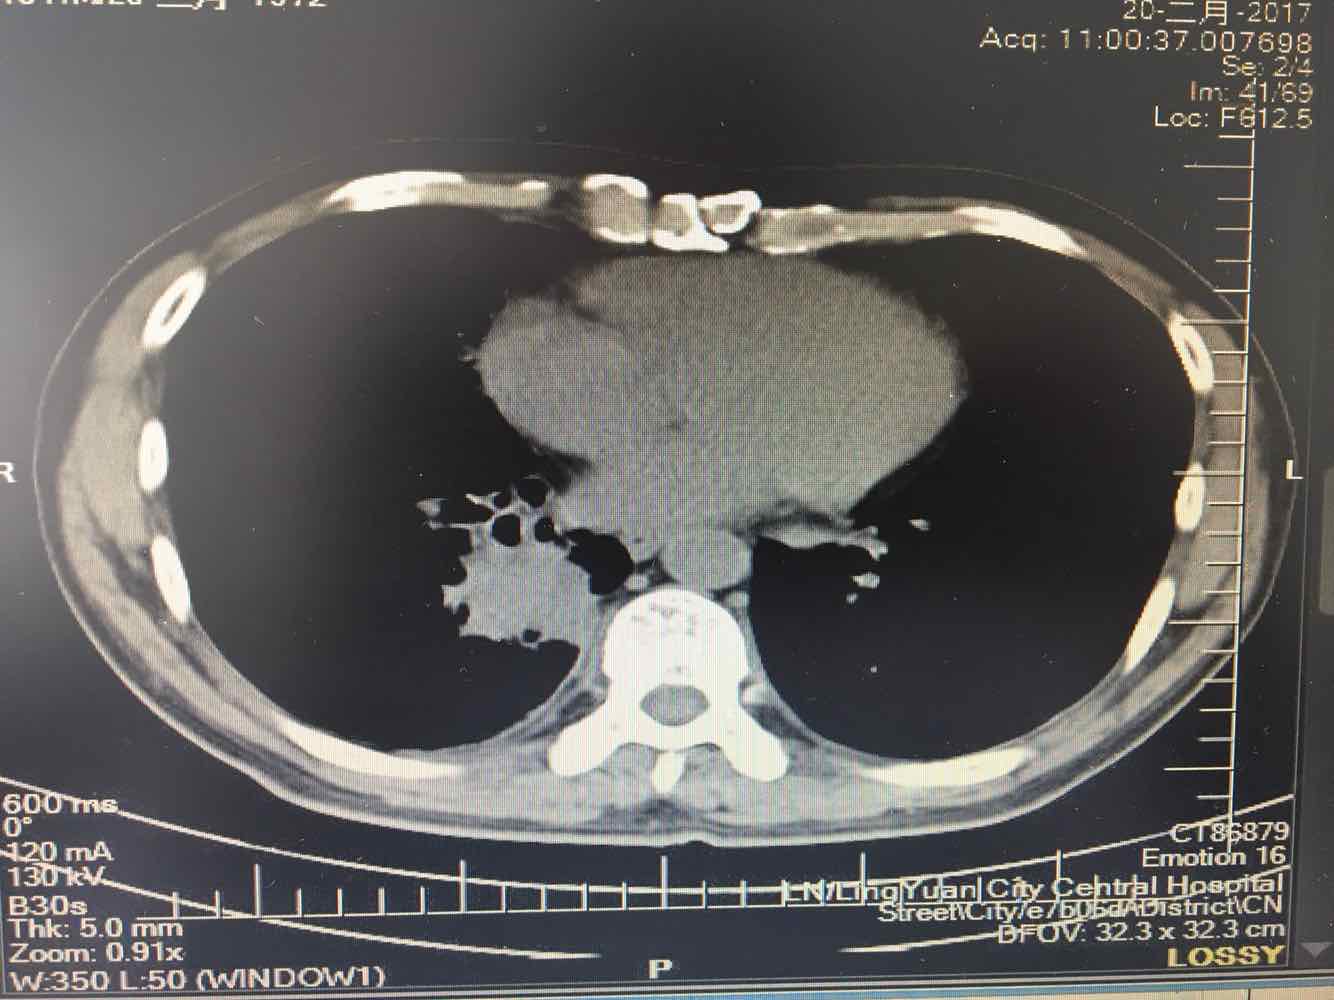

男,45岁,咳嗽,咳痰1个月,发热,盗汗,体重下降5公斤,肺结核病史30年.右肺下叶病变性质待查?